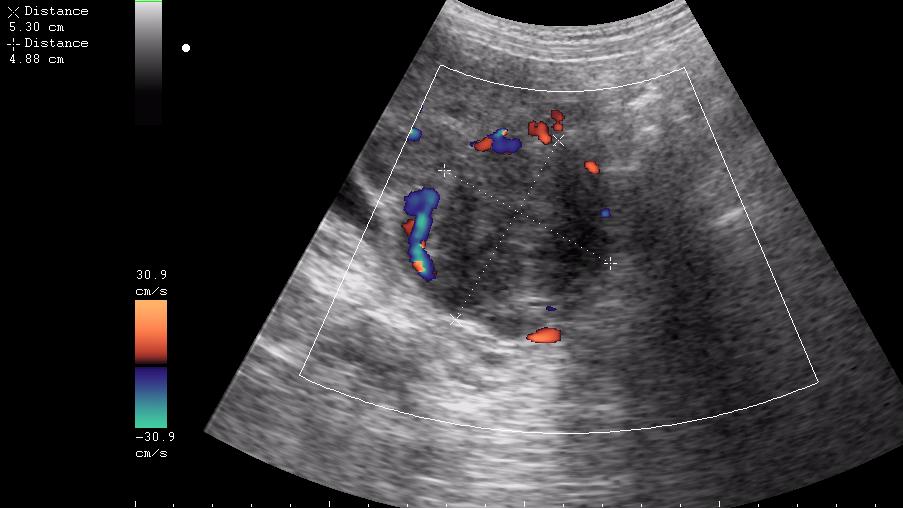

Почти как на сайте Марио,только возраст другой.Солидное гипоэхогенное негомогенное образование в области придатка слева довольно сложной структуры с усилением(?) кровотока по периферии-я за рак яичника

ещё раз - это матка 23-летней девушки. то есть, ВСЁ это, то что Вы видите, да-да, на весь экран - это матка.

Диагноз - фиброматоз. направлена строго на север и налево. к соседям. (онкодиспансер)

ну вот куда здесь ставить бодимаркер и какой?